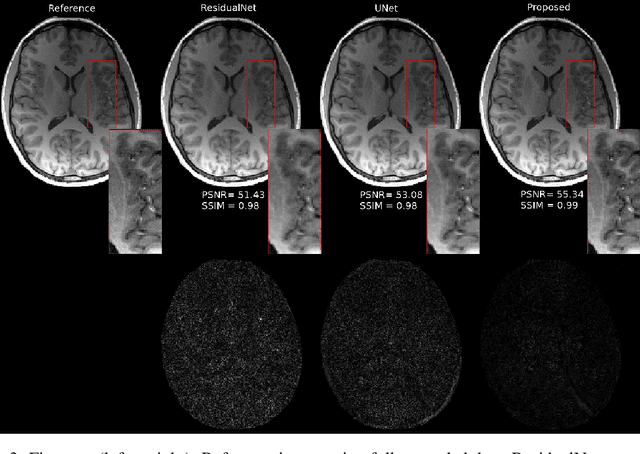

Fast data acquisition in Magnetic Resonance Imaging (MRI) is vastly in demand and scan time directly depends on the number of acquired k-space samples. The data-driven methods based on deep neural networks have resulted in promising improvements, compared to the conventional methods, in image reconstruction algorithms. The connection between deep neural network and Ordinary Differential Equation (ODE) has been observed and studied recently. The studies show that different residual networks can be interpreted as Euler discretization of an ODE. In this paper, we propose an ODE-based deep network for MRI reconstruction to enable the rapid acquisition of MR images with improved image quality. Our results with undersampled data demonstrate that our method can deliver higher quality images in comparison to the reconstruction methods based on the standard UNet network and Residual network.